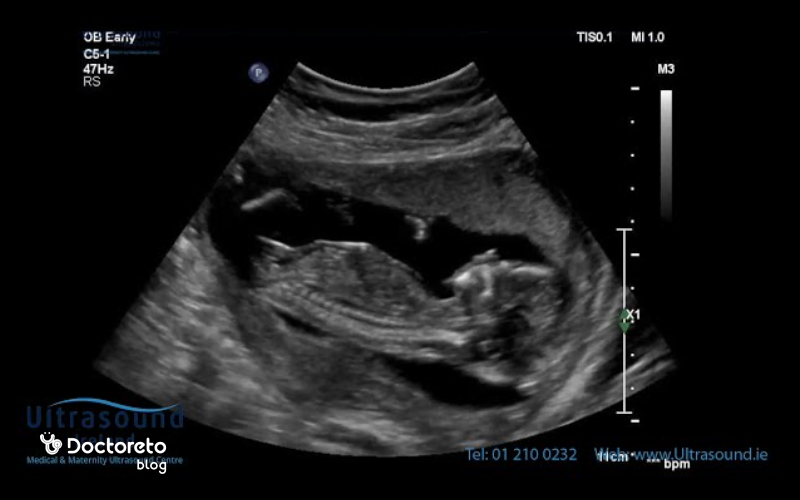

سونوگرافی در هفته پانزدهم بارداری

اگر سونوگرافی در هفتههای قبل انجام شده باشد، احتمالا تا هفته ۱۸ بارداری نیازی به سونوگرافی نباشد. در این هفته هنوز نمیتوان جنسیت جنین را تشخیص داد. برای تعیین جنسیت باید در هفته ۱۸ تا ۲۰ بارداری اقدام کنید. اگر پزشک در هفته ۱۵ بارداری جنسیت را اعلام کند، باید بدانید که احتمال خطا بالا است.

در بسیاری از موارد جنسیت جنین در هفته پانزدهم بارداری قابل تشخیص است، زیرا اندامهای جنسی خارجی تا حد زیادی شکل گرفتهاند. در سونوگرافی دقیق، بهویژه در مراکز مجهز و با دستگاههای پیشرفته، پزشک میتواند تفاوت بین اندام تناسلی پسر و جنین دختر در هفته پانزدهم بارداری را تشخیص دهد. با این حال، وضعیت قرارگیری جنین، ضخامت جفت یا مقدار مایع آمنیوتیک ممکن است تشخیص را دشوار کند. اگر در این هفته جنسیت مشخص نشود، معمولاً در سونوگرافی هفتههای ۱۸ تا ۲۰ بهصورت دقیقتر قابل مشاهده است. برای اطمینان قطعی، میتوان از آزمایشهای ژنتیکی مانند NIPT یا آمنیوسنتز استفاده کرد که از هفته نهم بارداری به بعد انجام میشوند.

در هفته پانزدهم بارداری، جنین بهطور فعال در رحم حرکت میکند، اما این حرکات هنوز بسیار ظریف و غیرقابلاحساس برای مادر هستند. در این مرحله، عضلات و مفاصل جنین قویتر شدهاند و او میتواند دستها و پاهای خود را خم و راست کند، سرش را بچرخاند و حرکات بلع یا مکیدن را تمرین کند. گاهی در سونوگرافی، حرکات شبیه کشوقوس یا چرخیدن دیده میشود. مادرانی که قبلاً باردار بودهاند ممکن است زودتر از دیگران این حرکات خفیف را احساس کنند، اما معمولاً در هفتههای ۱۸ تا ۲۰ حرکات جنین بهطور واضحتر قابلدرک میشوند.